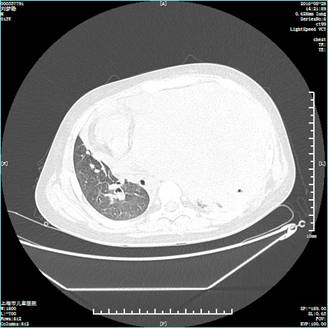

近日,一名十岁男童检查出胸腔内有20cm×15cm×5cm巨大肿瘤,这个和一部电话座机差不多大小的肿瘤几乎占满了孩子整个左侧胸腔,并与周围的身体组织发生粘连,辗转多家医院后收治于上海市儿童医院进行手术。手术历时5小时,经过肿瘤切除术、肺叶修补术、胸膜剥脱术、膈肌折叠术等多个手术,成功切除了这个压在患儿一家心上的“包袱”。

左侧胸腔肿瘤将心脏都挤压“挪位”

上海市儿童医院心胸外科主任张儒舫收治了小文,凭借多次切除胸腔巨大肿瘤手术以及丰富的心胸外科手术经验,快速为小文进行了敲定了手术时间。报告显示,小文胸腔内肿瘤尺寸约20cm×15cm×5cm,约是一个家用座机电话的大小,在胸腔内与心脏、肺、膈肌等组织粘连,其中与肺粘连的程度最深,从而导致此次手术难度巨大,因为稍有不慎就会触及到肺及其周围的血管和神经,从而引起各类严重的术后并发症。此外,由于肿瘤与肺融合粘连严重,与胸腺、膈肌、心包融合粘连,因此这不只是一个简单的肿瘤切除手术,还要完成肺叶修补术、胸膜剥脱术、膈肌折叠术等多项手术。手术于当天下午三点半正式开始,一直持续到晚上8点才结束,历时5个小时,对于医生的专业能力和体能都有一定的考验。值得庆幸的是肿瘤的存在并没有影响到小文其他脏器的功能,粘连严重的左肺功能良好,现如今卸下胸中“包袱”的小文已经出院,进入了康复阶段。